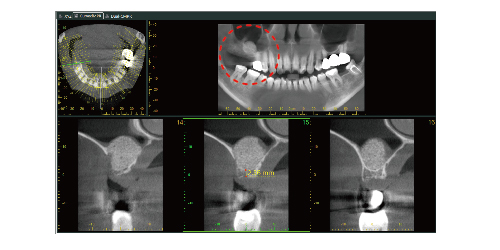

▲紅圈處為進行「上顎竇增高術」,提供足夠的骨量

透過上顎竇增高術補骨後,臼齒區便能植入既粗且長的穩固植體,這不僅改善了咀嚼功能,更提升了整體口腔健康與美觀,臨床影像也能清楚顯示手術效果:在手術前,X光片顯示骨量不足,無法進行植牙;而在手術完成並成骨後,影像中可見骨頭已恢復足夠高度,成功植入長度適當的人工牙根。這些案例證明,上顎竇增高術能有效解決骨量不足的問題,並大幅提升植牙成功率。【註7】